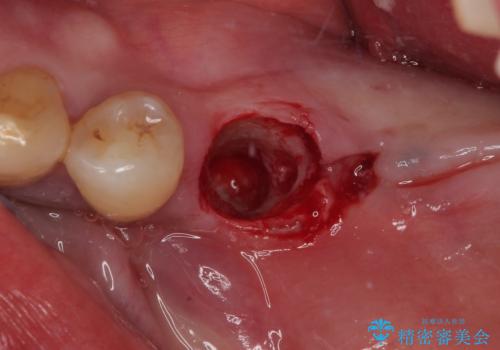

骨吸収が甚大な後方は3ヶ月ほど待機して、手前は抜歯即時埋入により、短期間インプラント補綴治療を行うこととしました。

なお、後方の歯は痛みが酷かったため、初診時に抜歯をすることとなりました。